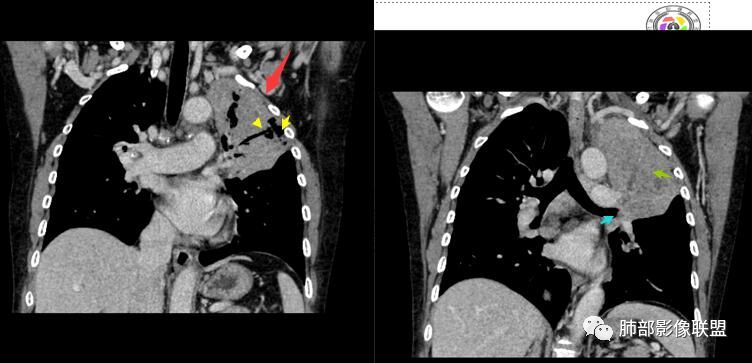

整个上叶尖后段阻塞性肺不张的表现,从强化来看没有异常结节状或肿块样强化,肿块内部点状钙化、纵隔多发小淋巴结、下叶背段有树芽征,整体来看支持肺结核,让人不放心的是最后一幅冠状位重建的图像尖后段支气管堵了,而且有轻度的隆起,所以很难除外粘液表皮样癌(女性,鳞癌可能性小),如果是我写报告肯定会建议纤支镜检查

考虑结核伴混合感染。中青年女性,持续低热、不正规抗感染症状加重。左上肺低密度肿块,左上固有段支气管未显影(结核侵蚀干酪样坏死),左上舌段支气管通畅但增厚变形。左下肺树芽征新发支气管播散。鉴别:粘液腺癌

看这些钙化

前壁不厚,附近钙化灶太多,所以觉得结核一定要考虑,加上树芽征,就更支持。

支气管因为软骨,密度偏高,从这连续性看,支气管这一段的壁不厚,只是周围有病灶。

支气管壁软骨存在且连续,没有被破坏掉,支气管壁局部通畅,提示支气管壁没破坏,那么近端支气管癌肿不考虑。远端有树丫征,病灶周围很多钙化,所以结核一定有。